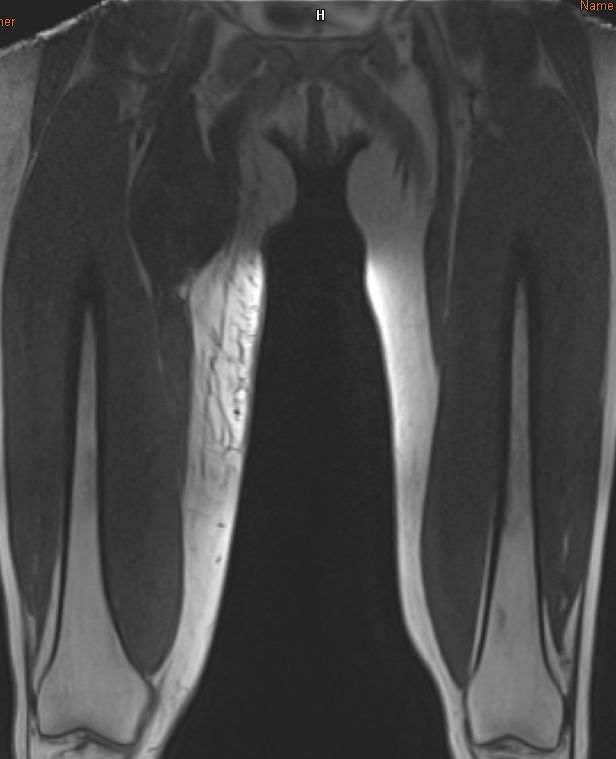

| Oberschenkel | 49-jährige Frau mit einem myxoiden Liposarkom der rechten Adduktoren-Loge.![]() |

Die enge Lagebeziehung zur A. femoralis ist gut erkennbar.![]() ![]() |

Frontale Schnittrichtung